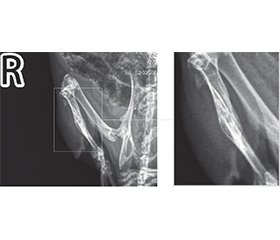

Актуальність. На сучасному етапі продовжуються експериментальні дослідження та клінічні спостереження з метою розробки нових методів лікування для покращення загоєння переломів кісток. В епоху зростання захворюваності на первинні злоякісні й метастатичні пухлини кісток, а також у часи травматичної епідемії під час війни вивчення можливостей впливу на перебіг кісткової репарації з метою її прискорення або покращення є обґрунтованим напрямом експериментальних досліджень. Мета: вивчити вплив модулюючих факторів — інфрачервоного лазерного випромінювання, кальцитоніну та пробіотика на основі Bifidobacterium animalis — на загоєння кісткового дефекту в експерименті in vivo. Матеріали та методи. В експерименті in vivo вивчено репаративний остеогенез у 32 тварин (щури Wistar), великогомілкову кістку яких травмували стоматологічним буром, використовуючи кетаміновий наркоз. Вплив модулюючих факторів на формування кісткової мозолі оцінювали за допомогою дослідження ушкоджених кінцівок тварин з використанням рентген-діагностичної системи Toshiba Radrex потужністю 80 кВт із дозою випромінювання при цифровій рентгенографії 0,03 мЗв; укладка вентродорсальна (на животі, спиною наверх), а також права латеральна (бокові зйомки). Результати. Дослідження показало, що формування кісткової мозолі під впливом лазера йде активно, але нелінійно і не завжди симетрично, що перекликається з результатами, отриманими в інших дослідженнях. У цій роботі вперше приділено увагу вивченню поєднаного впливу одразу декількох модулюючих факторів на репаративний остеогенез, а саме лазерного випромінювання, гормону кальцитоніну й пробіотика. Слід зазначити, що максимальний стимулюючий вплив на формування кісткової мозолі в експериментальних тварин спостерігався в групі «лазер + кальцитонін», що можна охарактеризувати навіть як надмірну репаративну активність кісткової тканини. Натомість у групах, де був присутній пробіотик, репаративний остеогенез у щурів проходив більш гармонійно, демонструючі кращі рентгенологічні результати, як, наприклад, у групі «кальцитонін + пробіотик» і особливо в групі, де препарат B.animalis був поєднаний із лазером та введенням кальцитоніну. Можна обґрунтовано припустити, що здатність B.animalis нормалізувати кальцієвий метаболізм створює умови для репаративного остеогенезу, максимально наближеного до фізіологічного сценарію. Висновки. Поєднання кальцитоніну з пробіотиком, а також лазерного випромінювання з кальцитоніном і пробіотиком сприяло гармонійному репаративному остеогенезу, що підтверджується відповідною рентгенологічною картиною. Здатність B.animalis зменшувати інтенсивність системного запалення, а також модулювати всмоктування кальцію з кишечника і впливати на його метаболічні шляхи може бути передумовою досягнення повноцінної кісткової репарації.

Background. At the present stage, experimental studies and clinical observations are continuing to develop new treatment methods for improvement of bone fracture healing. In the era of increasing incidence of primary malignant and metastatic bone tumors, as well as in times of traumatic epidemics during the war, studying the possibilities of influencing the course of bone repair in order to accelerate or improve it is a justified direction of experimental research. Objective: to study the influence of modulating factors — infrared laser radiation, calcitonin and probiotic based on Bifidobacterium animalis — on the healing of a bone defect in an in vivo experiment. Materials and methods. Reparative osteogenesis was studied in 32 animals (Wistar rats) whose tibia were injured with a dental drill using ketamine anesthesia. The influence of modulating factors on the formation of bone callus was assessed by studying the injured limbs of animals using the Toshiba Radrex X-ray diagnostic system, with a power of 80 kW, a radiation dose during digital radiography of 0.03 mSv, ventrodorsal positioning (on the stomach, back up), as well as right lateral (side views). Results. The study showed that the formation of bone callus under the influence of the laser is active, but nonlinear and not always symmetrical, which is in line with the results obtained in other studies. Instead, this work for the first time paid attention to the study of the combined effect of several modulating factors on reparative osteogenesis, namely laser irradiation, calcitonin and probiotic. It should be noted that we observed the maximum stimulating effect on the formation of bone callus in experimental animals in the laser + calcitonin group, which can even be characterized as excessive reparative activity of bone tissue. On the other hand, in the groups where a probiotic was present, reparative osteogenesis in rats proceeded more harmoniously, demonstrating better radiological results, such as in the calcitonin + probiotic group and especially in the group where the B.animalis preparation was combined with laser and calcitonin administration. It can be reasonably assumed that the inherent ability of B.animalis to normalize calcium metabolism creates conditions for reparative osteogenesis, as close as possible to the physiological scenario. Conclusions. The combination of calcitonin with a probiotic, as well as laser irradiation with calcitonin and a probiotic promoted harmonious reparative osteogenesis, which is confirmed by the corresponding radiological picture. The ability of B.animalis to reduce the intensity of systemic inflammation, to modulate calcium absorption from the intestine and influence its metabolic pathways may be a prerequisite for achieving complete bone repair.